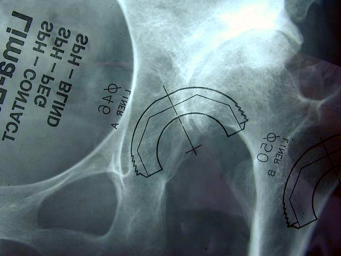

髋臼重建基本原则髋臼位置-优化-活动度/稳定性-45~55度外展

-15~20度前倾-根据解剖

基本原则----髋臼定位和方向

解剖标志

-横韧带

-髋臼周缘的骨性结构

-真髋臼底